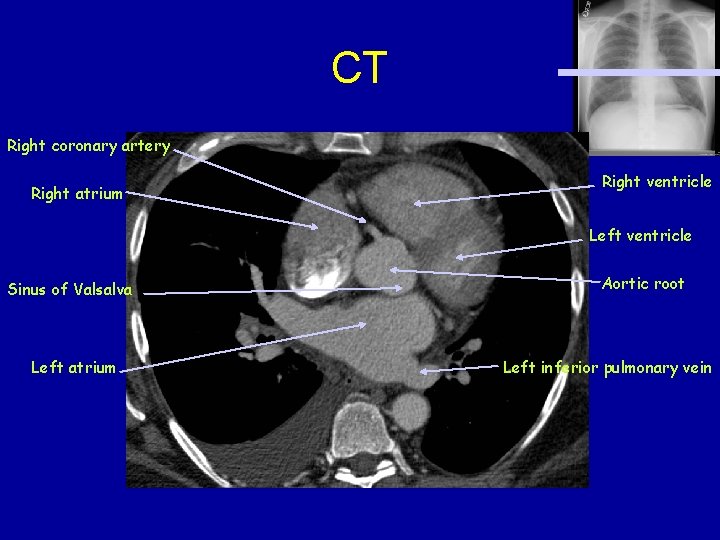

CT Right coronary artery Right atrium Right ventricle Left ventricle Sinus of Valsalva Left atrium Aortic root Left inferior pulmonary vein